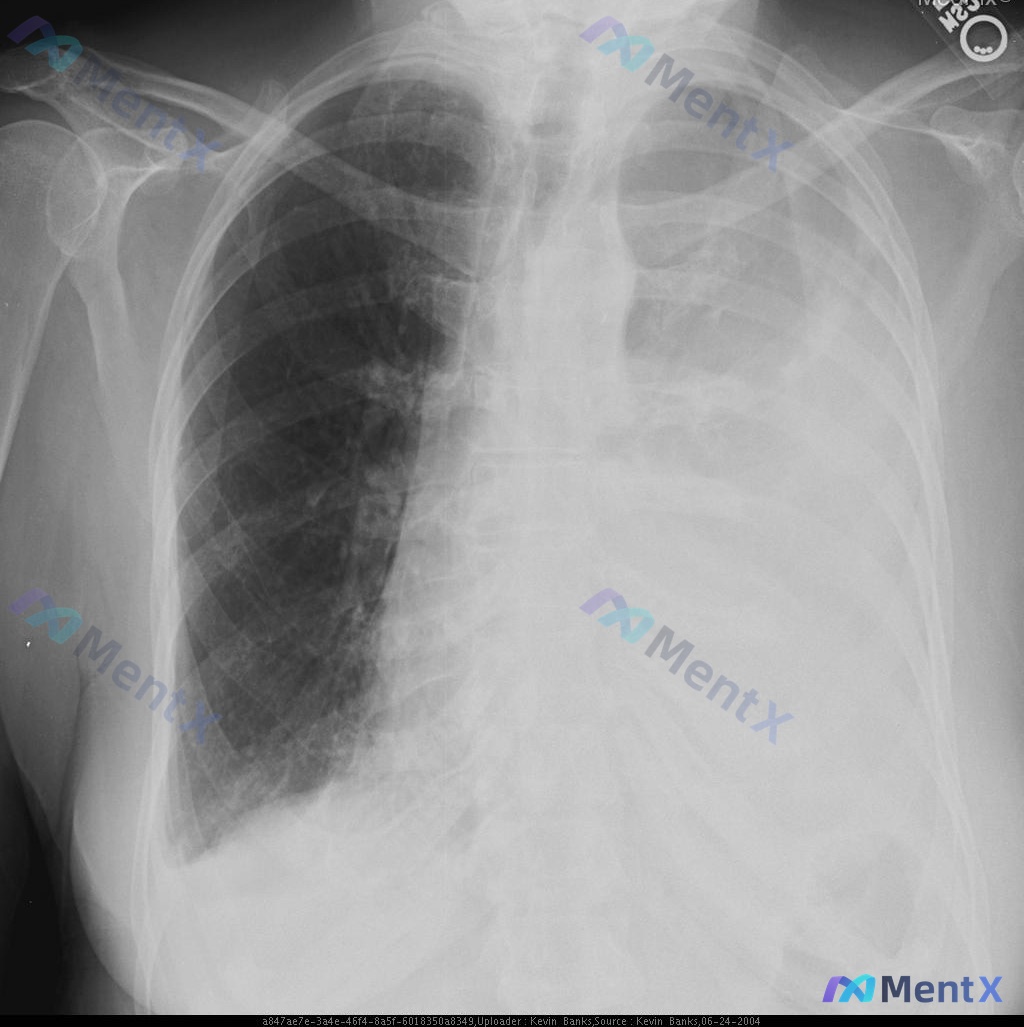

复查胸片(仰卧位AP位)

- 左侧胸腔大面积高密度实变影,几乎占据整个左侧肺野,左侧心缘、膈肌轮廓消失

- 气管、纵隔明显向右侧移位

- 右侧肺野透亮度相对增高